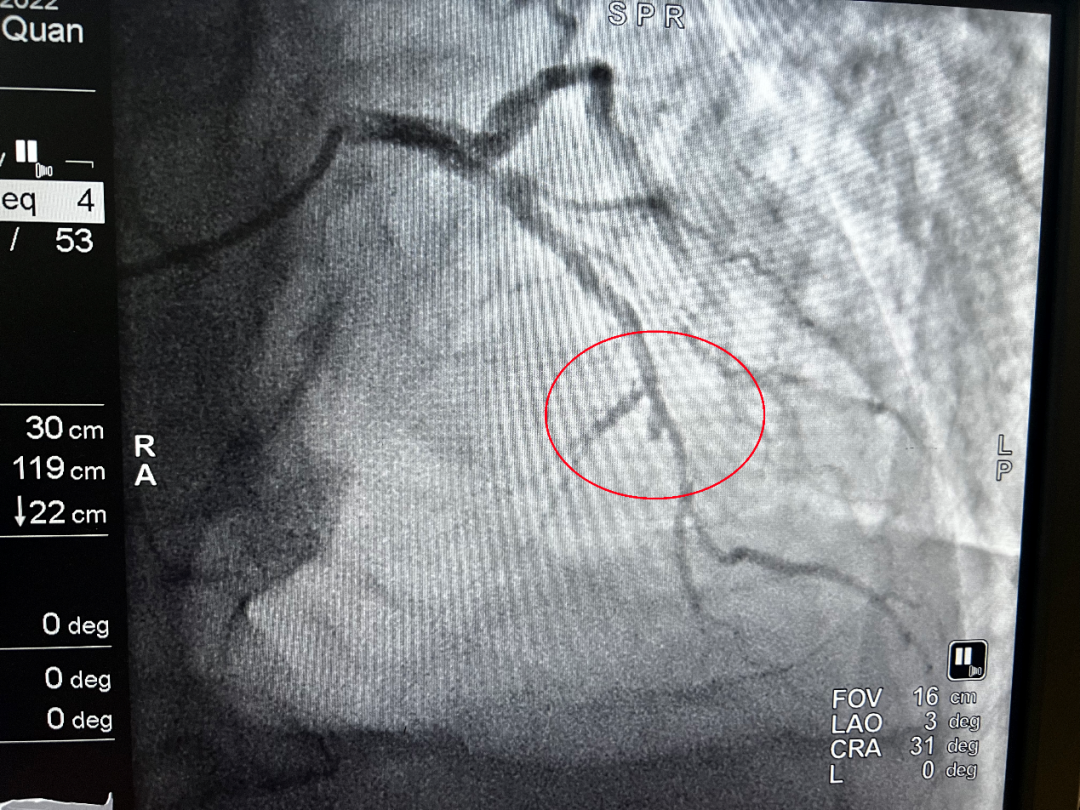

“启动导管室,医生已到位,穿好防护服。”11月14日凌晨1点21分,重庆医科大学附属璧山医院(重庆市璧山区人民医院)心血管内科副主任闫庆凯给介入导管室主管护师谭小利发去信息,准备开展急诊介入手术。